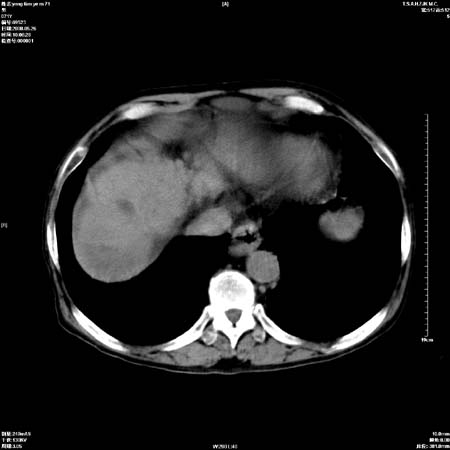

以下是引用医影拾贝在2008-6-5 22:48:00的发言:[br]肝硬化、门脉高压、胃底食管静脉曲张、低蛋白血症(胆囊壁水肿、增厚)、腹水[br]脾功能亢进、脾大、脾、左肾囊肿[br]肝囊性占位、不除外肝脓肿可能[br]建议增强以除外肝右叶肝ca可能

以下是引用chenglinhunan在2008-6-5 22:53:00的发言:[br]1. 肝硬化腹水,脾肿大。[br]2. 肝右后叶占位,肝癌。[br]3。建议ct增强扫描。

以下是引用xulianj在2008-6-5 21:40:00的发言:[br]支持肝硬化腹水;建议增强。肝、脾、肾囊肿待排。

以下是引用zjzjr在2008-6-6 12:34:00的发言:[br]1. 肝硬化腹水,脾肿大。[br]2. 肝右后叶占位,肝癌。[br]3。建议ct增强扫描。[br]4肝脾囊肿.